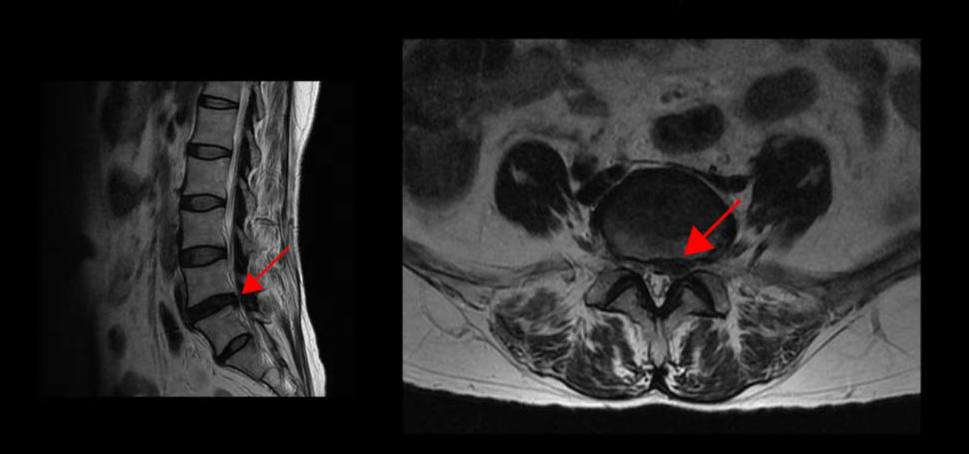

<4-5번 디스크 파열>

이 환자분은 4, 5번 디스크가 파열되어 다리로 가는 신경근을 자극해 왼쪽 엉덩이와 다리에 심한 방사통이 있는 상태였습니다. 디스크 파열이 아주 심한 상태는 아니었지만, 신경주사를 두 번 맞은 후 잠시 좋아졌다가 다시 통증이 몇 배 더 심하게 악화되었는데요. 이렇게 신경주사 치료로 통증이 잡히지 않으면 많은 분들이 시술이나 수술밖에 방법이 없다는 얘기를 듣게 되고, 이 환자분도 그런 얘기를 듣고 한방재활치료를 받기로 결심하셨습니다.